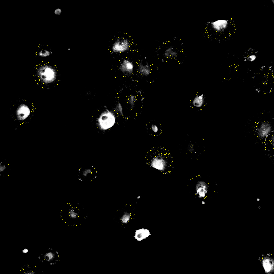

The IF Dots App provides dot detection per cell within the cell compartments for up to four markers in a sample (e.g., FISH, RNA, oil droplets). Each segmented cell compartment is measured for up to 20 intensity, statistic, and morphometric parameters. Dot measurement parameters are provided per cell compartment (e.g., nucleus, cytoplasm) and per dot and include count, mean intensity, total dot area, the sum of intensity.